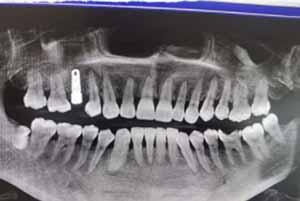

都说武汉萌芽齿科种牙技术好,不知道萌芽齿科看牙怎么样所以过来体验一下,因为龋齿导致一颗牙齿被拔除一直都缺一颗牙,吃饭什么的都很不方便,到萌芽齿科后见到了贺医生,贺医生从事口腔工作多年,种植经验也很丰富,做了检查后贺医生进行了即刻种植,做完手术后没有什么不适感,感觉还行。